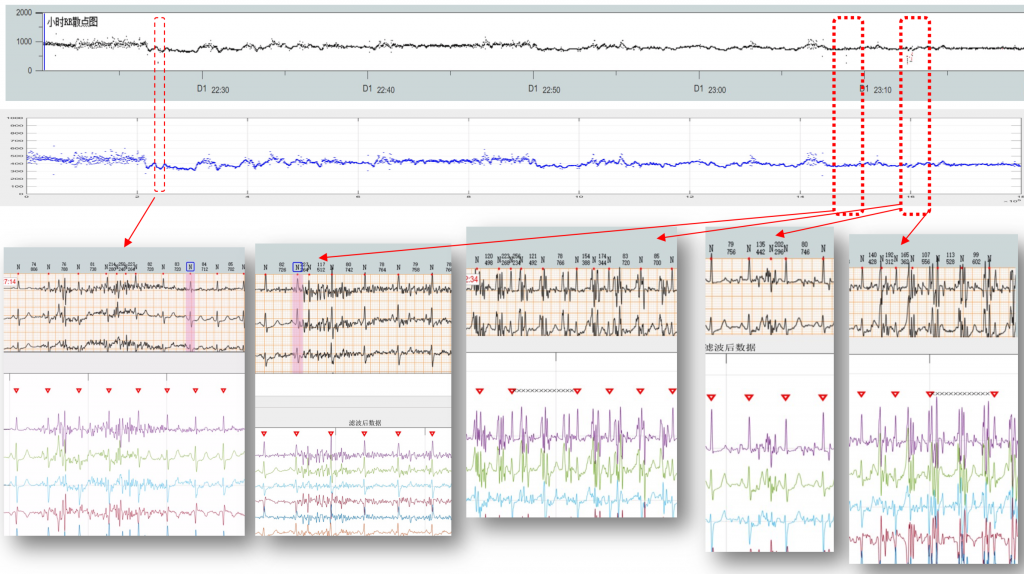

唯理科技发布了自研的24小时12导联心电图ECG的处理与分析算法,包含了信号的预处理,滤波、高鲁棒性的R峰识别、心律失常疾病的分类等Holter所需的算法。算法的实测效果得到了国产器械厂商到一致好评。R峰识别率大幅提升,大大节省了医生的时间。

目前唯理的算法已经跟随合作伙伴进入国内心血管一线医院中使用。

R峰识别准确率展示

唯理科技发布了自研的24小时12导联心电图ECG的处理与分析算法,包含了信号的预处理,滤波、高鲁棒性的R峰识别、心律失常疾病的分类等Holter所需的算法。算法的实测效果得到了国产器械厂商到一致好评。R峰识别率大幅提升,大大节省了医生的时间。

目前唯理的算法已经跟随合作伙伴进入国内心血管一线医院中使用。

R峰识别准确率展示